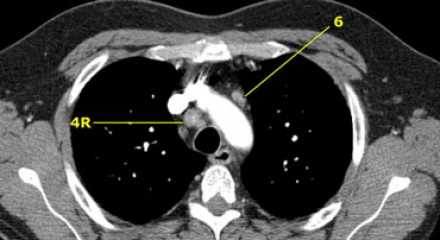

На изображении слева мы видим 4R паратрахеальные узлы. Кроме того здесь представлен узел кнаружи от дуги аорты, то есть 6 группы.